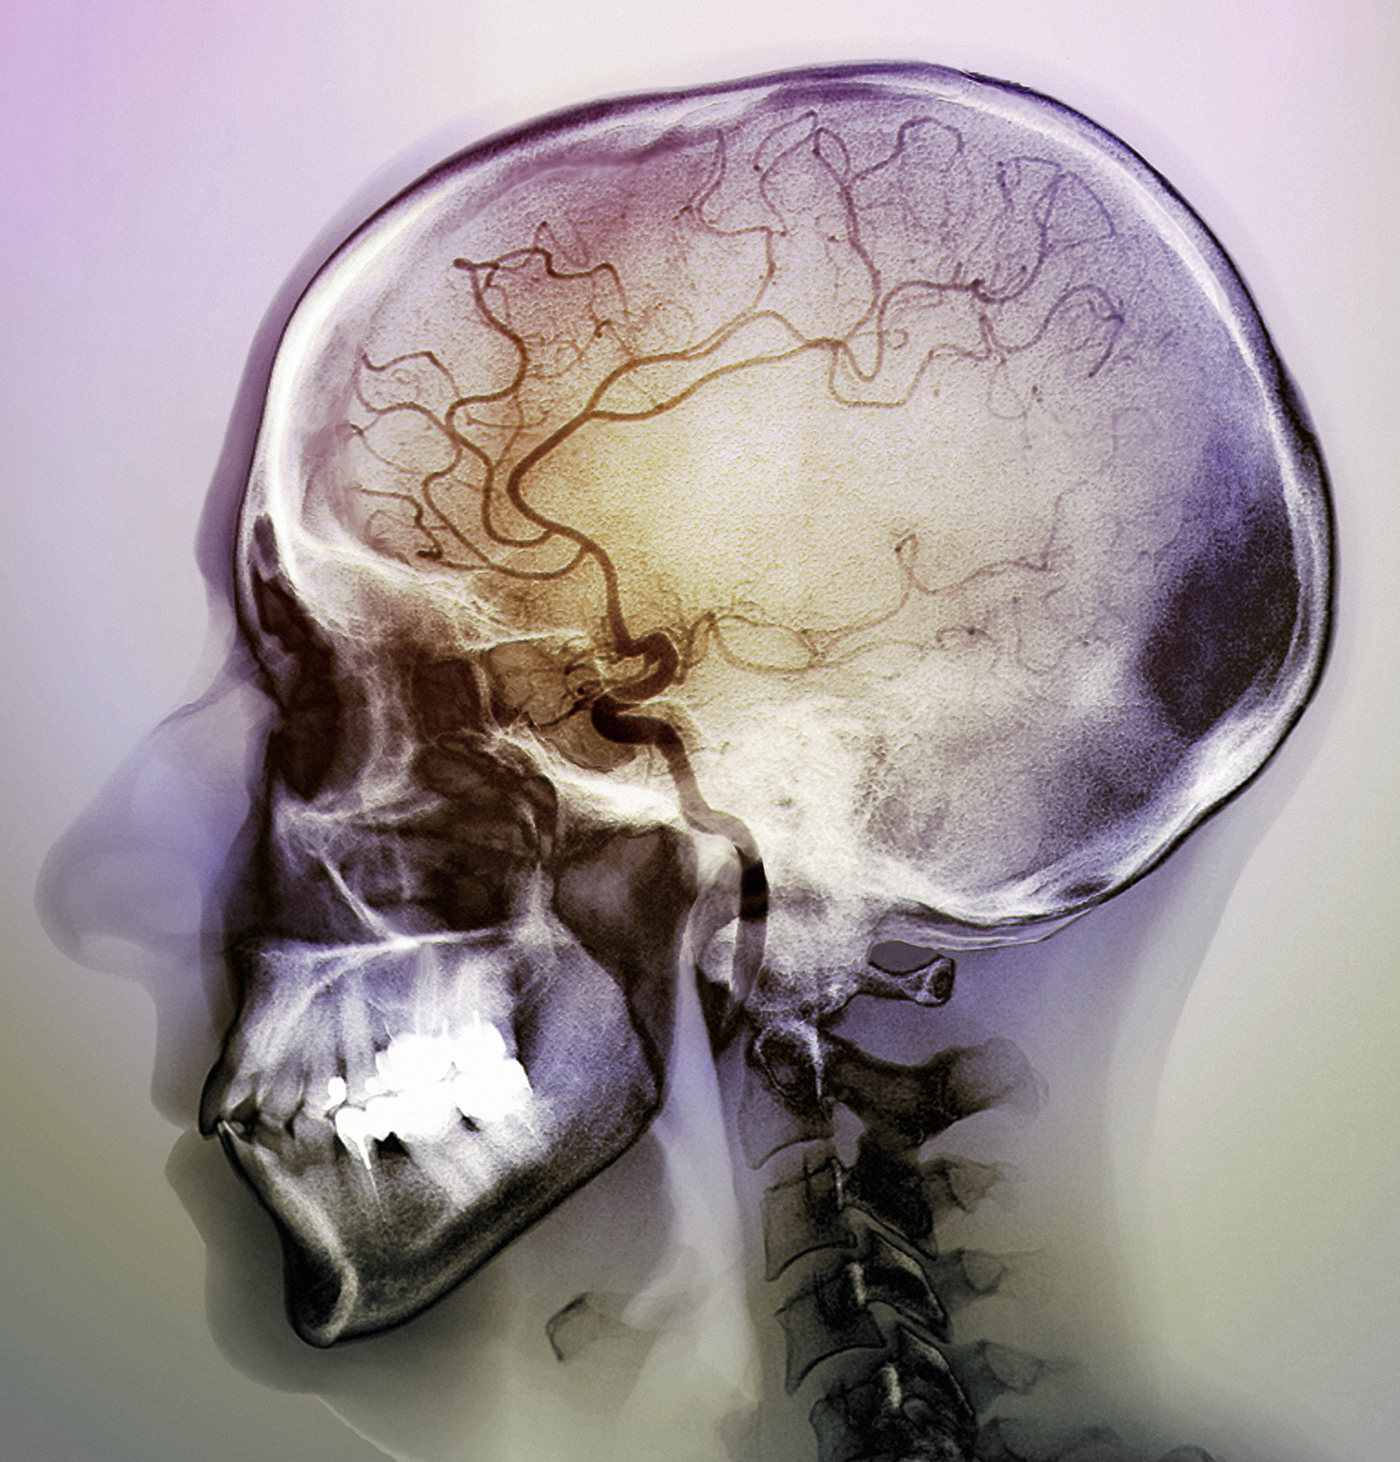

During an ischemic stroke, blocked arteries cause a lack of blood flow to parts of the brain, seen here in a 48-year-old patient. There are fewer blood vessels visible in the center of the brain.

Zephyr/Science Source